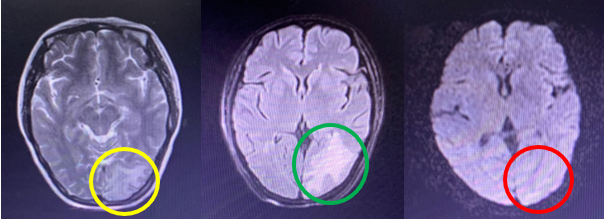

- Chụp cộng hưởng từ sọ não: Nhu mô não thùy chẩm trái có khối kích thước 17x21mm, đồng tín hiệu trên Flair, hạn chế khuếch tán trên DWI, phù não chất trắng diện rộng xung quanh, ngấm thuốc viền sau tiêm.

Hình 2: Hình ảnh chụp cộng hưởng từ sọ não: Nốt tổn thương ngấm thuốc thùy chẩm trái kèm phù não rộng xung quanh trên xung T2 (vòng tròn màu vàng), trên xung FLAIR (vòng tròn màu xanh), xung khuếch tán (vòng tròn màu đỏ).

- Chụp cộng hưởng từ sọ não: Nhu mô não thùy chẩm trái có khối kích thước 15x20mm, tăng nhẹ tín hiệu trên Flair, giảm tín hiệu trên T1W, sau tiêm ngấm thuốc viền, không hạn chế khuếch tán trên DWI, phù não chất trắng diện rộng xung quanh, ngấm thuốc viền sau tiêm.

Hình 4: Hình ảnh chụp cộng hưởng từ sọ não: Nốt tổn thương ngấm thuốc thùy chẩm trái kèm phù não rộng xung quanh trên xung T2 (vòng tròn màu vàng), trên xung FLAIR (vòng tròn màu xanh), xung khuếch tán (vòng tròn màu đỏ).